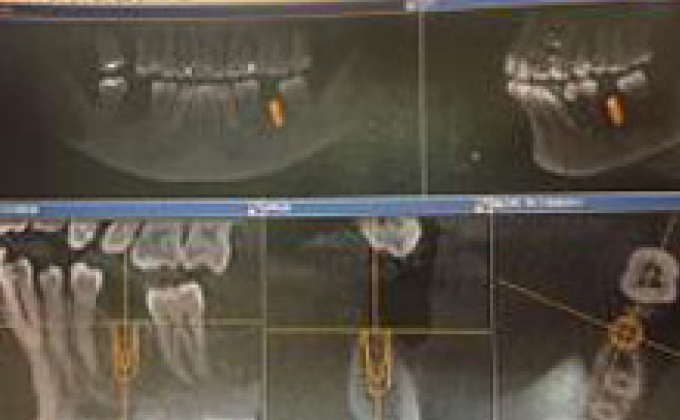

1. 安全・確実な手術のためにCT・模型で分析。詳細な手術ガイドを作成

安全・確実な手術のために、CT・模型で分析し、インプラント埋入方向を細かく決定した手術ガイドをつくり、さらに手術前に模型上で試してから本番の手術を行なっています。インプラントレポートを配布しています。

①診断

②ステント

③CT分析

出血・神経マヒ防止のために当院では、通常のレントゲン以外に大学病院でCTを必ず撮影して、放射線科の医師と連携し血管・神経までの距離と 骨幅を限り無く正確に測定し、太い神経・血管とインプラントの距離(安全域)を通常よりもさらに1~3mm多くとってインプラントを埋入しています。